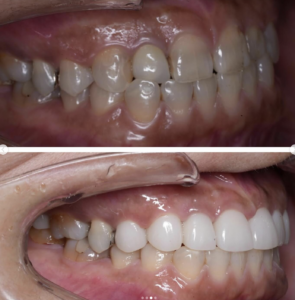

噛み合わせから審美的なところまで、トータルで治療させて頂いた患者様です。

ここまでやるとなると、できないクリニックもありますし、できるところでも年単位でかかってしまうクリニックが大半だと思いますが、今回は4月末にカウンセリングでご来院いただき、5月に治療をスタートして9月末には診療が終わっています。

治療回数や、治療期間がかかってしまうと、患者様も通院が辛くなったり疲れてしまったりしてしまうと思います。どんどん綺麗になっていく、食事がしやすくなっていくという実感がある方が患者様に楽しく治療に臨んでいただけると思うので、私は診療のスピード感を大切にしています。

トータルでやらせていただいたので、噛み合わせなどの機能面から外見などの審美性もかなり良くなり、患者様にも満足して頂けてよかったです。

治療期間 約4ヶ月